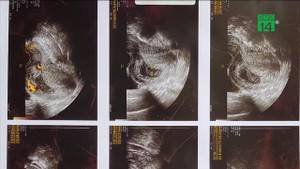

Một sản phụ người Campuchia vừa được các bác sỹ bệnh viện FV cứu chữa trong tình trạng chảy máu không ngừng sau ca sinh mổ từ quê nhà, tính mạng nguy cấp.